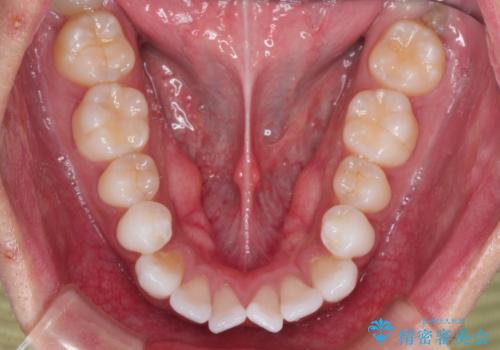

治療完了後、重なり合っていた歯はきれいに整い、懸念されていた前歯の突出も一切起こることなく、理想的な噛み合わせを実現しました。装置が目立ちにくかったため、治療期間中も周囲の目を気にすることなく、前向きに治療に取り組んでいただくことができました。